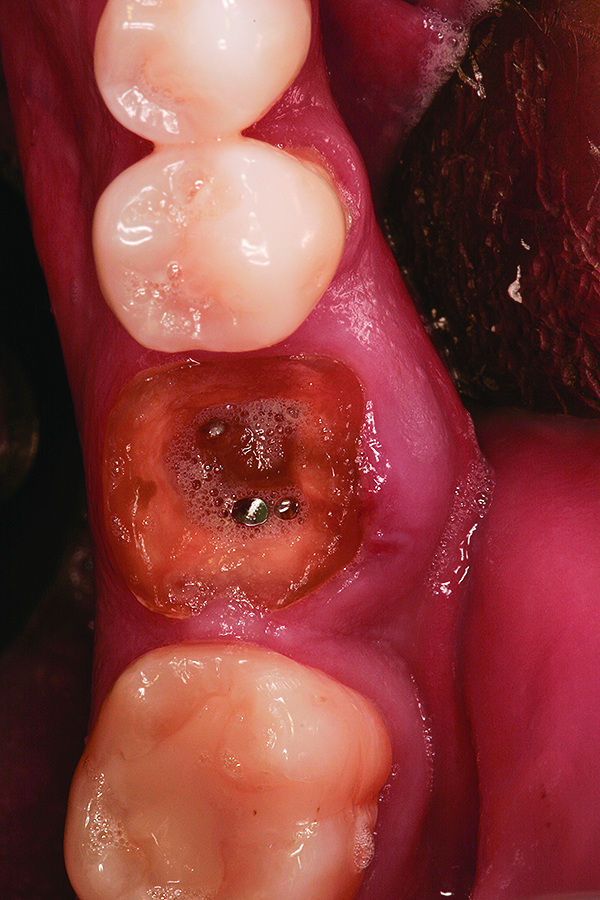

Fig 8. Case 2: Hopeless mandibular first molar prior to extraction.

Figure 8

Fig 9. Note the significant osseous defect in the buccal osseous wall following atraumatic tooth extraction.

Figure 9